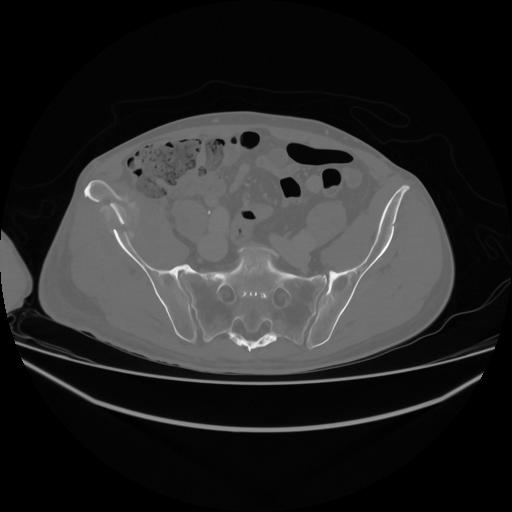

5 CUERPO,CE,Vol,1.0,CUERPO,,